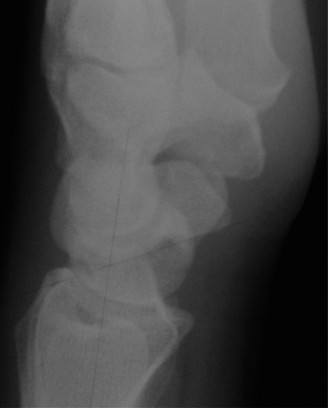

For the second patient, standard PA radiographs immediately reveal the diagnosis. We observe the classic Terry Thomas sign—a widening of the scapholunate interval greater than 3 mm. Furthermore, the lateral radiograph demonstrates a Dorsal Intercalated Segment Instability (DISI) deformity, characterized by a radiolunate angle greater than 15 degrees (lunate extended) and a scapholunate angle greater than 60 degrees.

Advanced imaging, particularly Computed Tomography (CT), is highly beneficial for preoperative templating. A fine-cut CT scan accurately maps the extent of the degenerative changes. In scapholunate advanced collapse (SLAC), arthritis follows a highly predictable, sequential pattern. It begins at the radial styloid-scaphoid articulation (Stage I), progresses to involve the entire radioscaphoid fossa (Stage II), and eventually encompasses the capitolunate joint as the capitate migrates proximally into the widened SL gap (Stage III). Notably, the radiolunate joint is universally spared in SLAC wrist due to the concentric, congruent nature of the lunate fossa and the preservation of the short radiolunate ligaments.